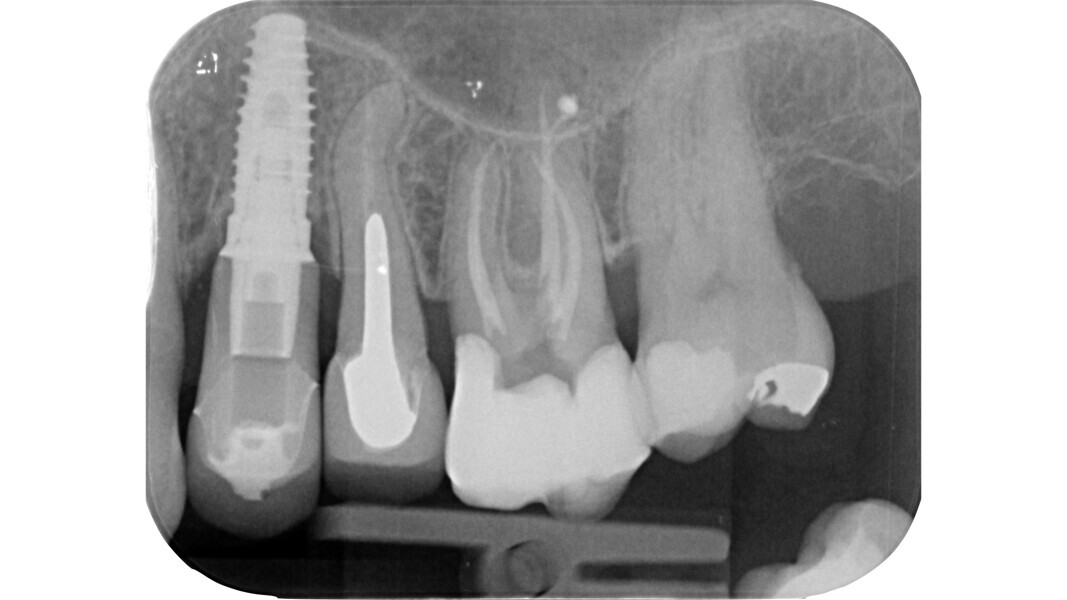

Parmi ces lois, certaines revêtent une importance clinique fondamentale. Par exemple, dans des conditions plus difficiles, telles que dans le cas d’une préparation dentaire prothétique, où les points de repère classiques sont perdus, la connaissance des trois premières lois nous permet de tracer une cavité d’accès qui suit le contour de la dent, et de repérer les orifices à l’intérieur de cette zone. D’un point de vue embryogénétique, la couronne dentaire est la projection du développement du tissu pulpaire.

Le principe du diamant fait référence à l’utilisation d’un certain type de fraise diamantée pour la phase de pénétration, en particulier dans les molaires supérieures et inférieures, ainsi que dans les prémolaires supérieures biradiculées. Deutsch8–9 associe des mesures morphologiques à la relation entre la surface occlusale, la hauteur, la position du plafond et du plancher de la cavité dans les dents pluriradiculées. Dans ces éléments, le plafond de la cavité pulpaire est situé au niveau de la JAC.

Dans les molaires, la distance entre la pointe d’une cuspide et le plafond de la cavité pulpaire est d’environ 6,3 mm, tandis que dans les prémolaires supérieures, elle est de 6,94 mm. La cavité pulpaire a une hauteur d’environ 1,5 à 2 mm et la distance moyenne entre le plancher de la cavité et la furcation est d’environ 3 mm (Tableau 1) (Fig. 13).